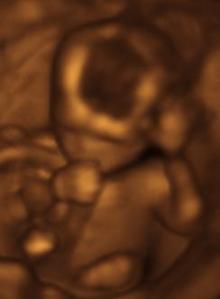

Baby at 13 weeks

Here is a beautiful video representing the miraculous formation of human life from conception. Right now, such precious lives hang in the balance. For years, the majority of our nation has turned the other way, pretending that abortion is merely a clinical procedure, that a fetus magically becomes a baby when it is wanted, yet reverts to a subhuman mass of tissue when it is not. Because of this, such hidden scenes of tender majesty are cut short in the butchery of abortion. (For those with cast iron stomachs, one can easily find videos online to confirm.)

In six and a half weeks, you had teeth buds. In two more, all your body systems were present. You could suck your thumb. By ten weeks, you could squint your tiny eyes, swallow, and move your tongue. Your fingers could grip. You were unborn. But you were there. Very human and very alive.

By your third month, you were breathing fluid. Soon you would be breathing air! At this point, you had fingernails. At week sixteen, you had eyelashes. By your fourth month after conception, you even had completely established fingerprints, and your taste buds were in full working order. You were a wonder in the works, though hidden in a veil of flesh.